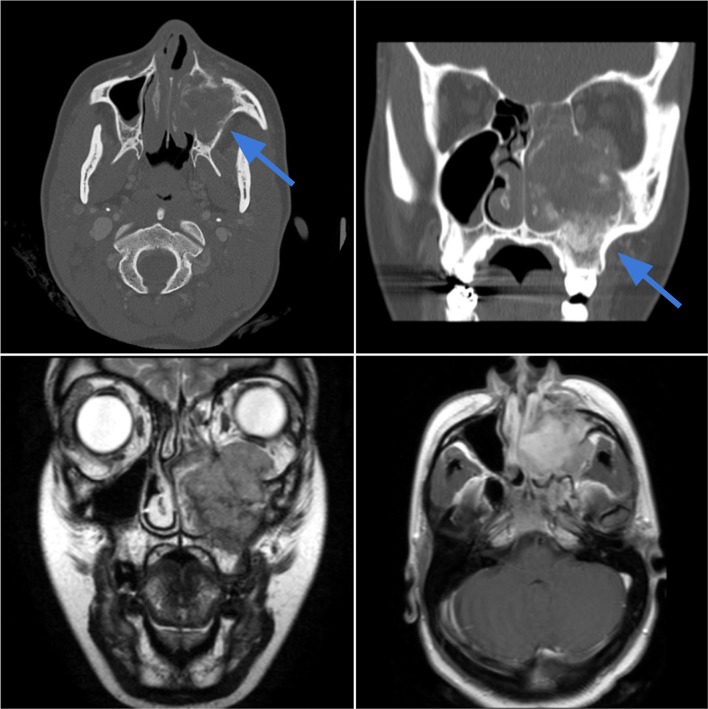

Case 2.

Chondrosarcoma of the larynx in an 80-year-old male with an incidental laryngeal mass found at intubation for knee surgery. Axial CT image in bone window (top left) demonstrates an expansile lesion with ring-and-arc chondroid-type calcifications (blue arrow) arising from the left cricoid cartilage with glottic and subglottic airway narrowing. On axial T2-weighted (top right), T1-weighted pre-contrast (bottom left) and T1-weighted post-contrast (bottom right) images, the lesion demonstrates a lobulated appearance with heterogeneous T2 hyperintensity, T1 hypointensity, and mild heterogeneous enhancement